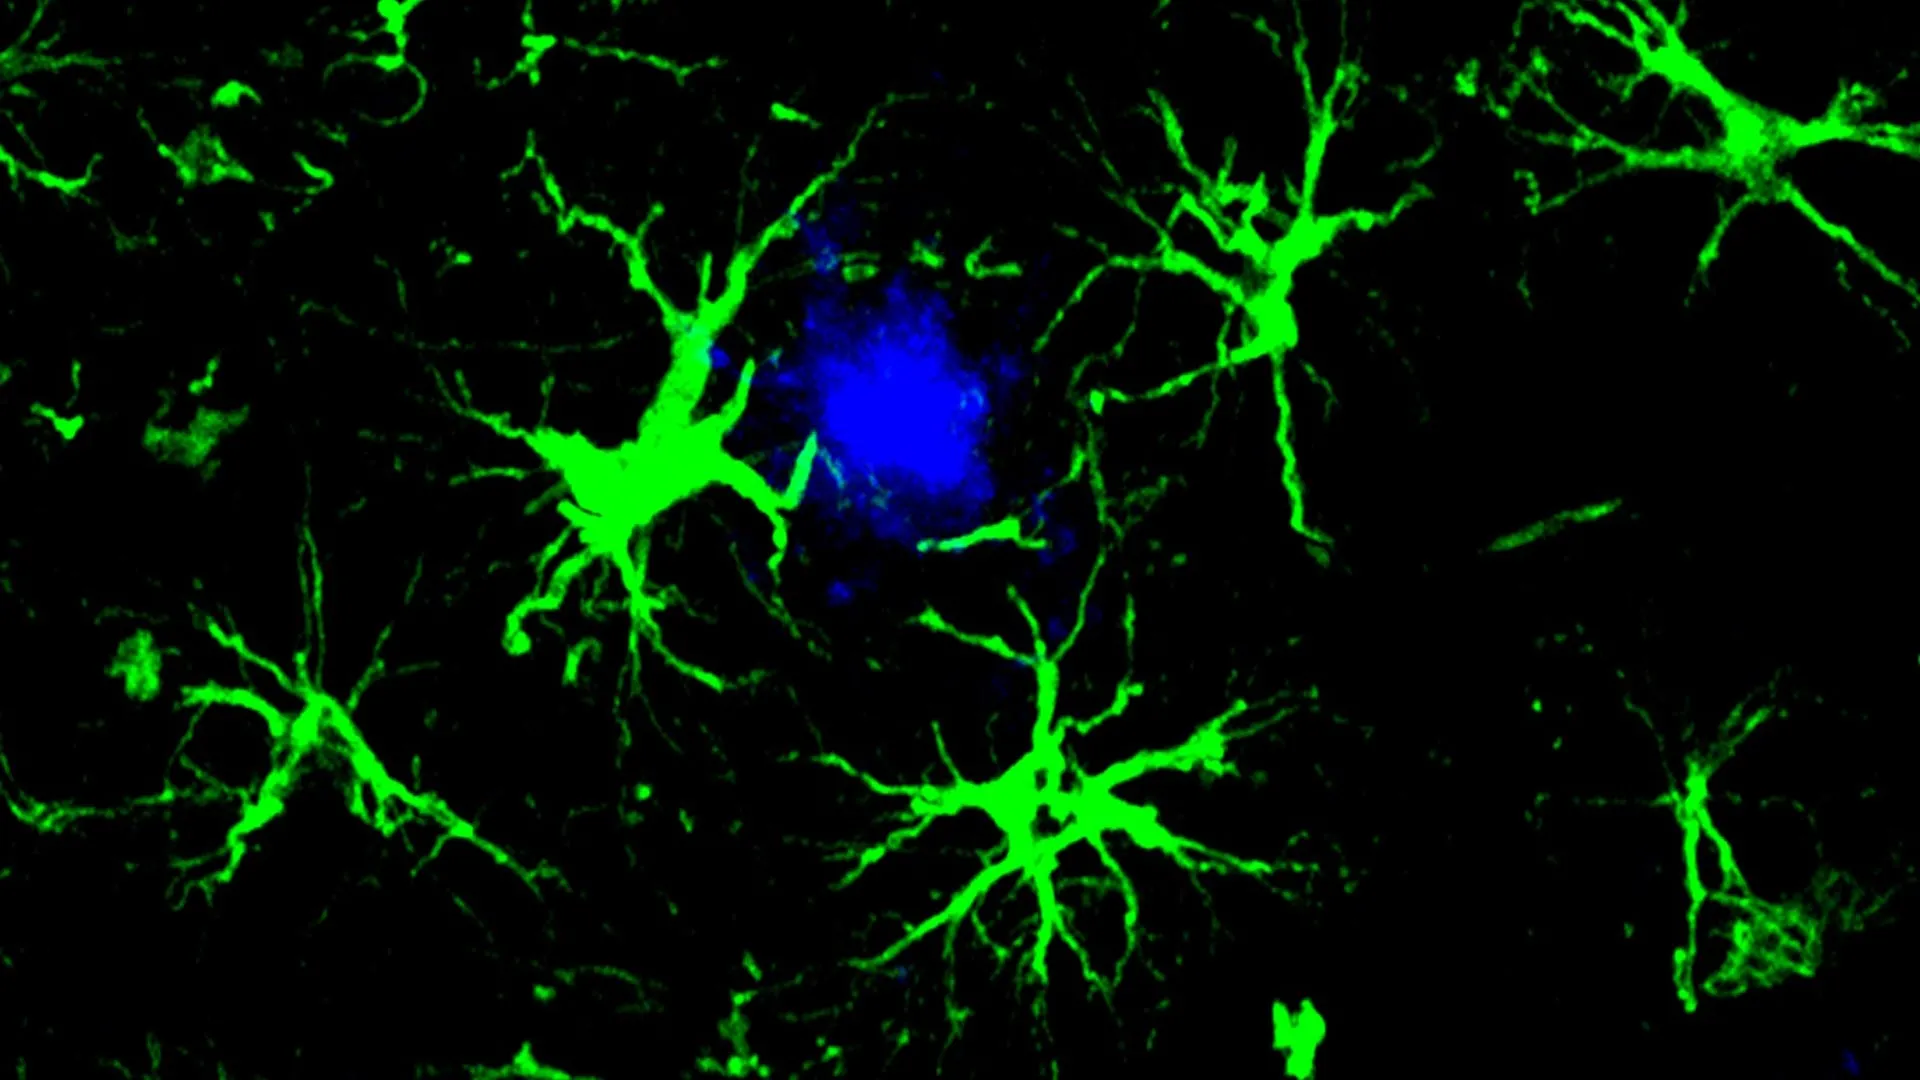

In applying this logic to Alzheimer’s, the research team, led by senior author Marco Colonna, MD, the Robert Rock Belliveau, MD, Professor of Pathology, and first author Yun Chen, PhD, decided against using T-cells. Instead, they turned their attention to astrocytes. Astrocytes are star-shaped glial cells that perform a variety of essential functions, including providing structural support, regulating the blood-brain barrier, and maintaining the chemical environment around neurons. Unlike T-cells, which are visitors to the brain, astrocytes are permanent residents, making them an ideal candidate for long-term, localized therapy.

Under normal circumstances, the brain relies on microglia—the primary immune cells of the central nervous system—to clear cellular debris and misfolded proteins. However, in the presence of Alzheimer’s disease, microglia often become overwhelmed. They can enter a state of chronic inflammation or become "exhausted," losing their ability to effectively phagocytose (engulf and digest) amyloid plaques. By reprogramming astrocytes, the researchers have essentially recruited a massive, untapped workforce to assist the failing microglia.

The engineered CAR-astrocytes are designed to capture and "swallow" amyloid-beta proteins. Because astrocytes are the most numerous cells in the brain, this strategy creates a ubiquitous defense network capable of monitoring the entire organ for the presence of harmful aggregates.